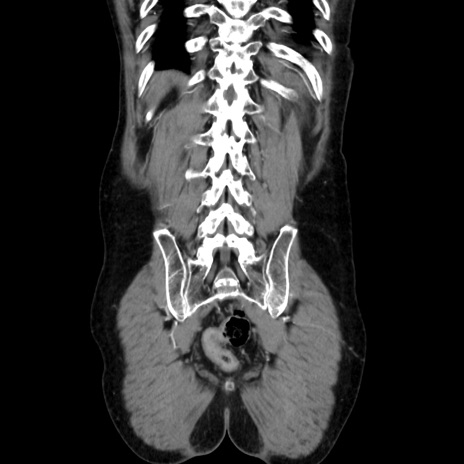

症例37(冠状断像)

【症例】40歳代 男性

【主訴】腹痛

【現病歴】4時間ほど前に電車に乗車中に臍部上より腹痛出現。徐々に増悪し起立困難となり、救急外来受診。生ものは数日食べていない。今朝お雑煮を食べた。

【身体所見】BT 36.8℃、BP 117/84mmHg、HR 91/min、SpO2 97%、苦悶様、腹部:臍上部広範囲圧痛あり、反跳痛±

【データ】WBC 8100、CRP 0.03